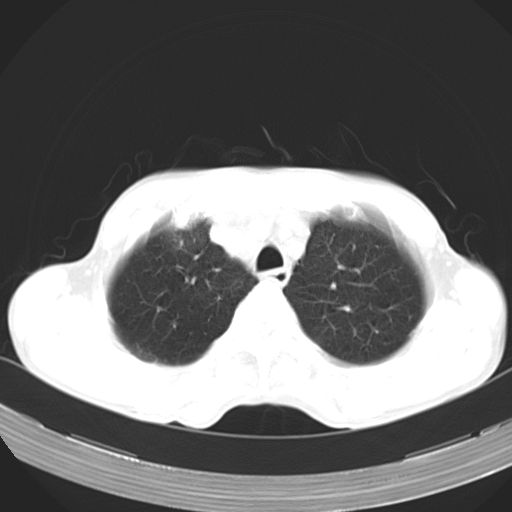

以下是引用zhangzhongshou在2007-5-24 12:55:00的发言:[br]1、右肺中叶中心型肺癌并右肺门、隆突下、纵隔淋巴结转移。右肺中叶阻塞性肺炎。

以下是引用苯小孩在2007-5-24 12:47:00的发言:[br]右侧肺门处不均匀密度软组织块影,远端肺组织见斑片模糊影,纵隔内淋巴结明显肿大,边界不清.<纵隔窗第12层面支气管内似见软组织结节>[br]考虑:1、右侧中央性肺癌并阻塞性肺炎并纵隔淋巴结转移可能性大.建议强化或纤支镜进一步检查.[br]2、隆突下淋巴结肿大/食道病变?请做鉴别检查.

以下是引用jw-830在2007-5-24 15:24:00的发言:[br][br] [br] 考虑右肺中央型肺癌并阻塞性炎症,右肺门及纵隔淋巴结转移。 [br] [br][br]